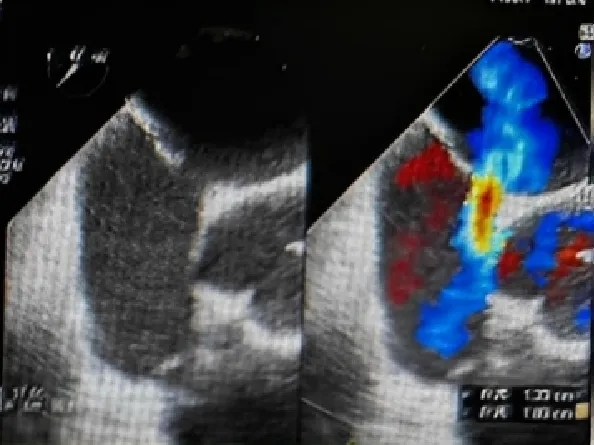

超声四腔心切面下可见封堵器双盘骑跨在房间隔两侧

锁定后超声多切面观察封堵器形态

四腔心切面

主动脉短轴切面

五腔心切面

封堵器锁定成型后,超声下多切面确认封堵器盘面贴合,稳定夹持缺损。